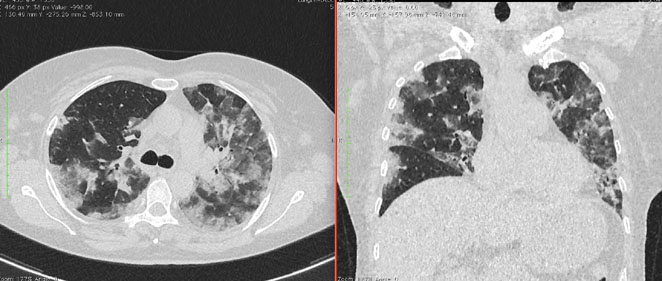

4.3. ЛУЧЕВАЯ ДИАГНОСТИКА COVID-19

Методы лучевой диагностики применяют для выявления COVID-19 пневмоний, их осложнений, дифференциальной диагностики с другими заболеваниями легких, а также для определения степени выраженности и динамики изменений, оценки эффективности проводимой терапии.

К методам лучевой диагностики патологии ОГК пациентов с предполагаемой/установленной COVID-19 пневмонией относят:

- Компьютерную томографию легких (КТ),

КТ имеет высокую чувствительность в выявлении изменений в легких, характерных для COVID-19. Применение КТ целесообразно для первичной оценки состояния ОГК у пациентов с тяжелыми прогрессирующими формами заболевания, а также для дифференциальной диагностики выявленных изменений и оценки динамики процесса. КТ позволяет выявить характерные изменения в легких у пациентов с COVID-19 еще до появления положительных лабораторных тестов на инфекцию с помощью МАНК. В то же время, КТ выявляет изменения легких у значительного числа пациентов с бессимптомной и легкой формами заболевания, которым не требуется госпитализация. Результаты КТ в этих случаях не влияют на тактику лечения и прогноз заболевания при наличии лабораторного подтверждения COVID-19. Поэтому массовое применение КТ для скрининга асимптомных и легких форм болезни не рекомендуется.

5. Рекомендовано проведение лучевого исследования пациентам при среднетяжелом, тяжелом и крайне тяжелом течении ОРИ с целью медицинской сортировки, оценки характера изменений в грудной полости и определения прогноза заболевания:

- выполнение КТ легких без внутривенного контрастирования в стационарных условиях или в амбулаторных - при показаниях к госпитализации;

15. Рекомендации по формированию описаний и оценке изменений в легких и ОГК при имеющейся/подозреваемой пневмонии COVID-19 представлены в Приложении 1.